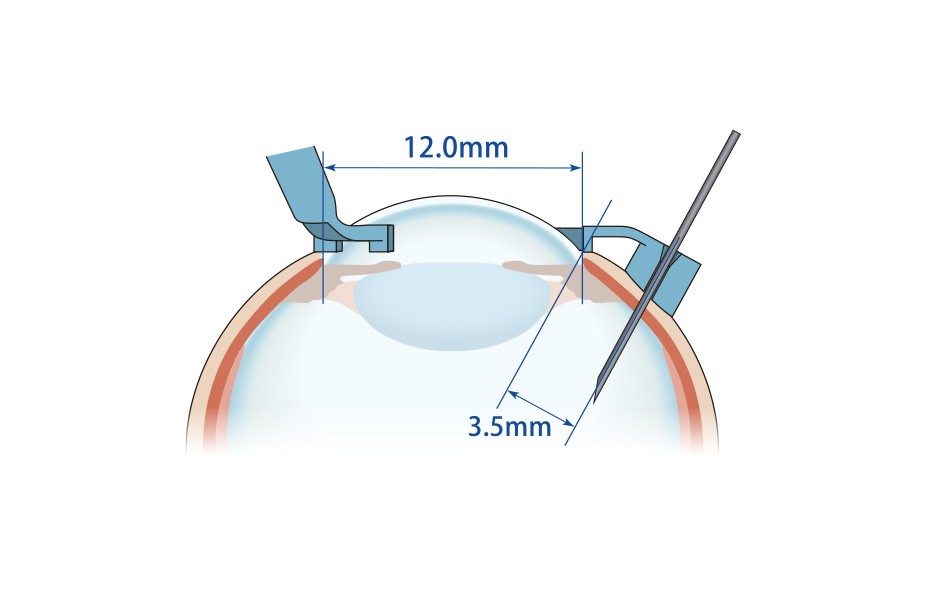

手順1:眼球の固定

■十分に開瞼します。

■角膜を中心に輪部全周にしっかりと押し当て注射ガイドを固定します。

手順2:注射針の刺入

■26G〜30G×3/4インチの鋭針をガイド孔に沿って刺入します。

■刺入部は輪部から3.5〜4.0mmになります。